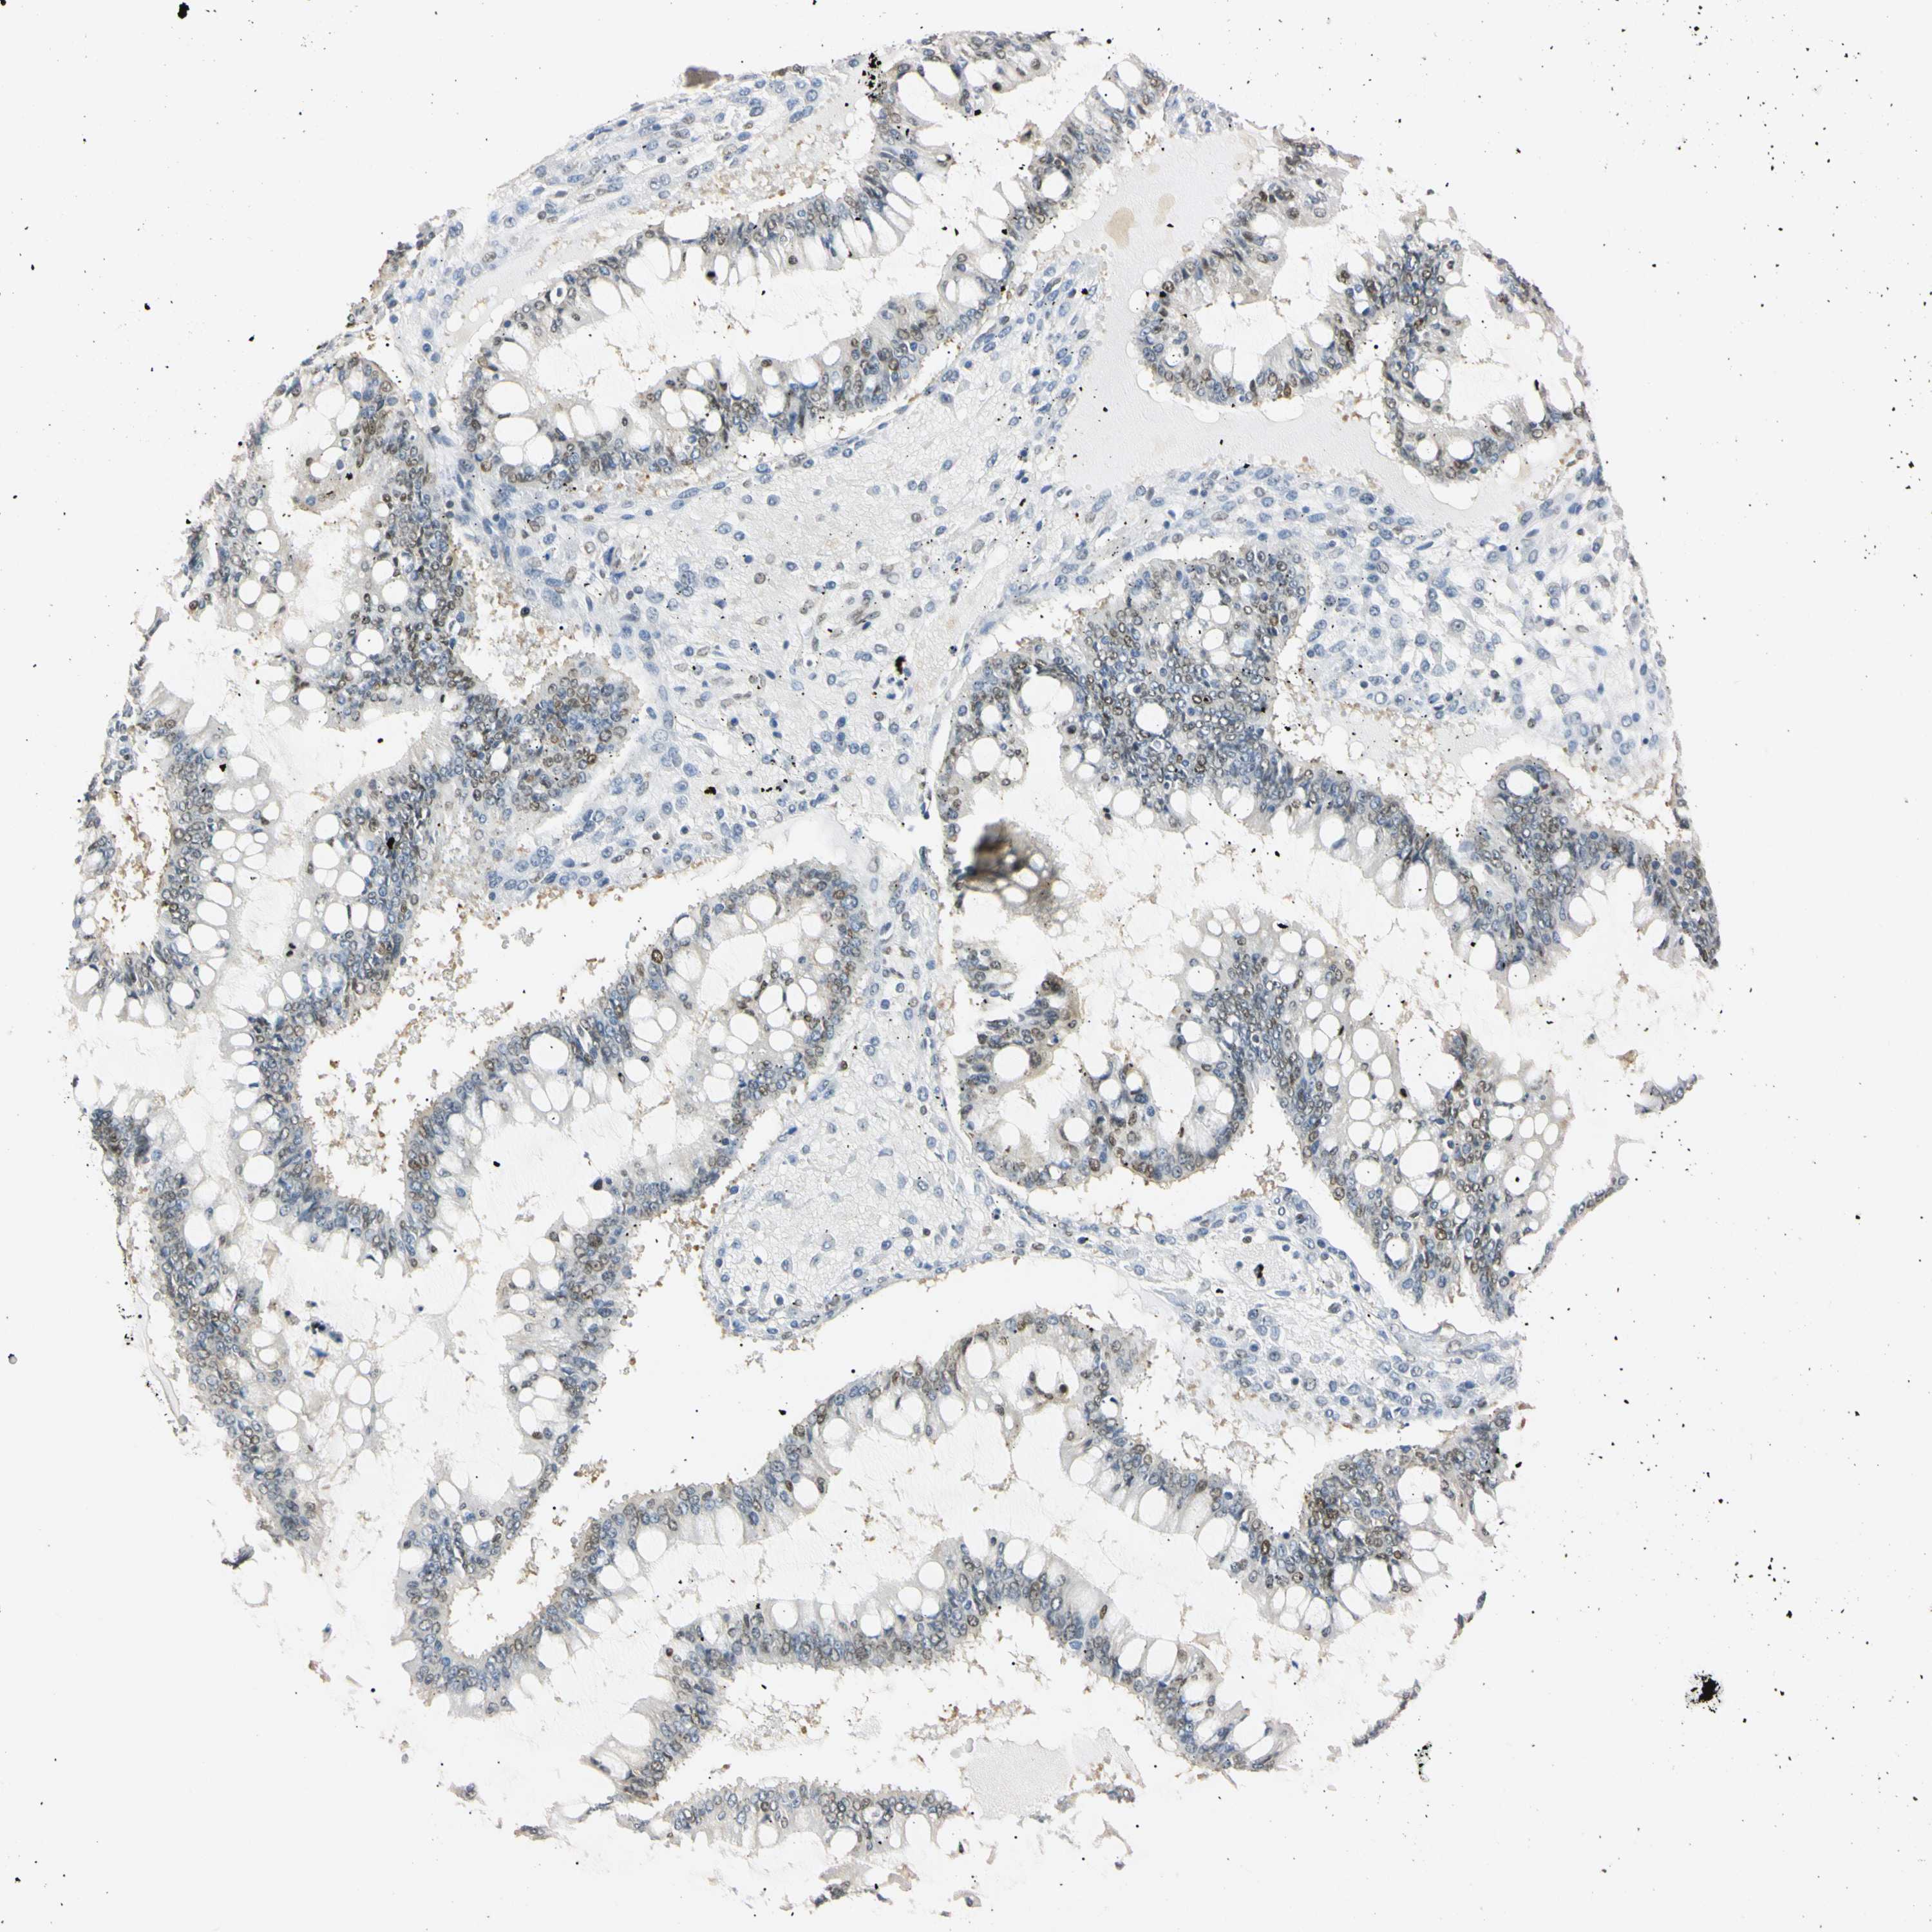

OVARIAN CANCER - Protein expressioni

A mouse-over function shows sample information and annotation data. Click on an image to view it in a full screen mode. Samples can be filtered based on level of antibody staining by selecting one or several of the following categories: high, medium, low and not detected. The assay and annotation is described here.

Note that samples used for immunohistochemistry by the Human Protein Atlas do not correspond to samples in the TCGA dataset.

Antibody stainingi

Antibody staining in the annotated cell types in the current human tissue is reported as not detected, low, medium, or high, based on conventional immunohistochemistry profiling in selected tissues. This score is based on the combination of the staining intensity and fraction of stained cells.

Each image is clickable and will lead to virtual microscopy that enables deeper exploration of all samples and also displays staining intensity scores, fraction scores and subcellular localization as well as patient and tissue information for each sample.

Antibody HPA008751

Antibody CAB005227

Carcinoma, endometroid